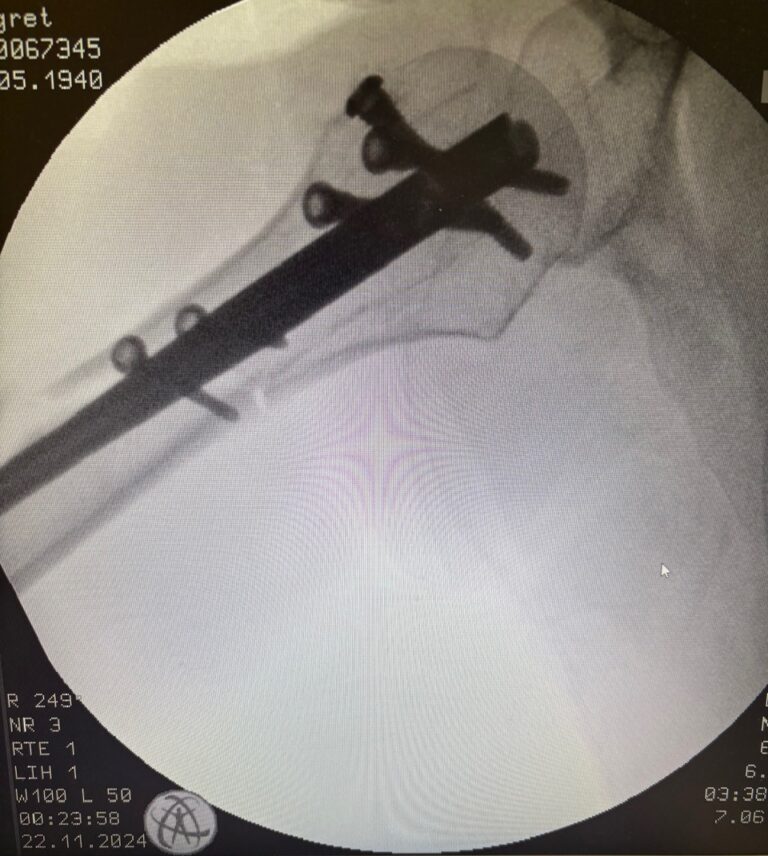

Χειρουργική

- Πλάκες, βίδες, ήλοι

- Ενδείκνυται σε ασταθή ή ανοικτά κατάγματα